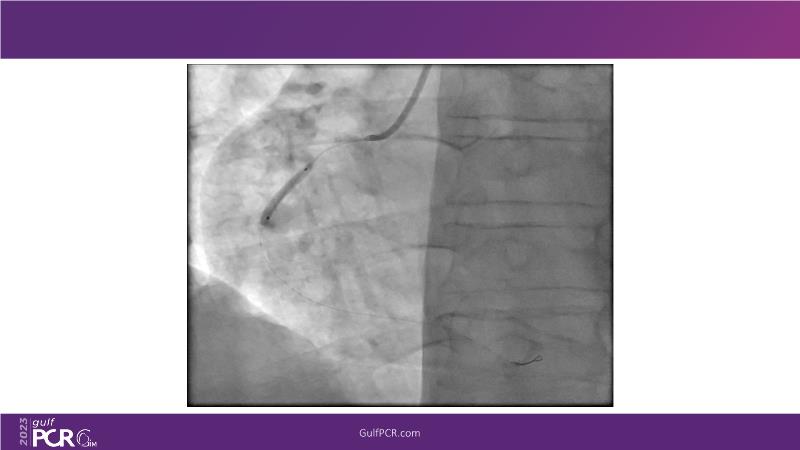

This session is a valuable resource for grasping innovative strategies in handling bifurcation and extended diffuse lesions through dedicated stenting solutions. Explore insights into the advanced Myval next-generation THV technology, unveiling its distinctive features, procedural advantages, and clinical outcomes across a diverse patient pool. Gain understanding into the CorAlign technique, ensuring accurate commissural and coronary alignment while maintaining coronary access. Additionally, delve into the techniques for precise sizing, positioning, and deploying of Myval THV.

- To understand novel tools and techniques for effective management of bifurcation lesions and long diffused lesions using dedicated stenting solutions